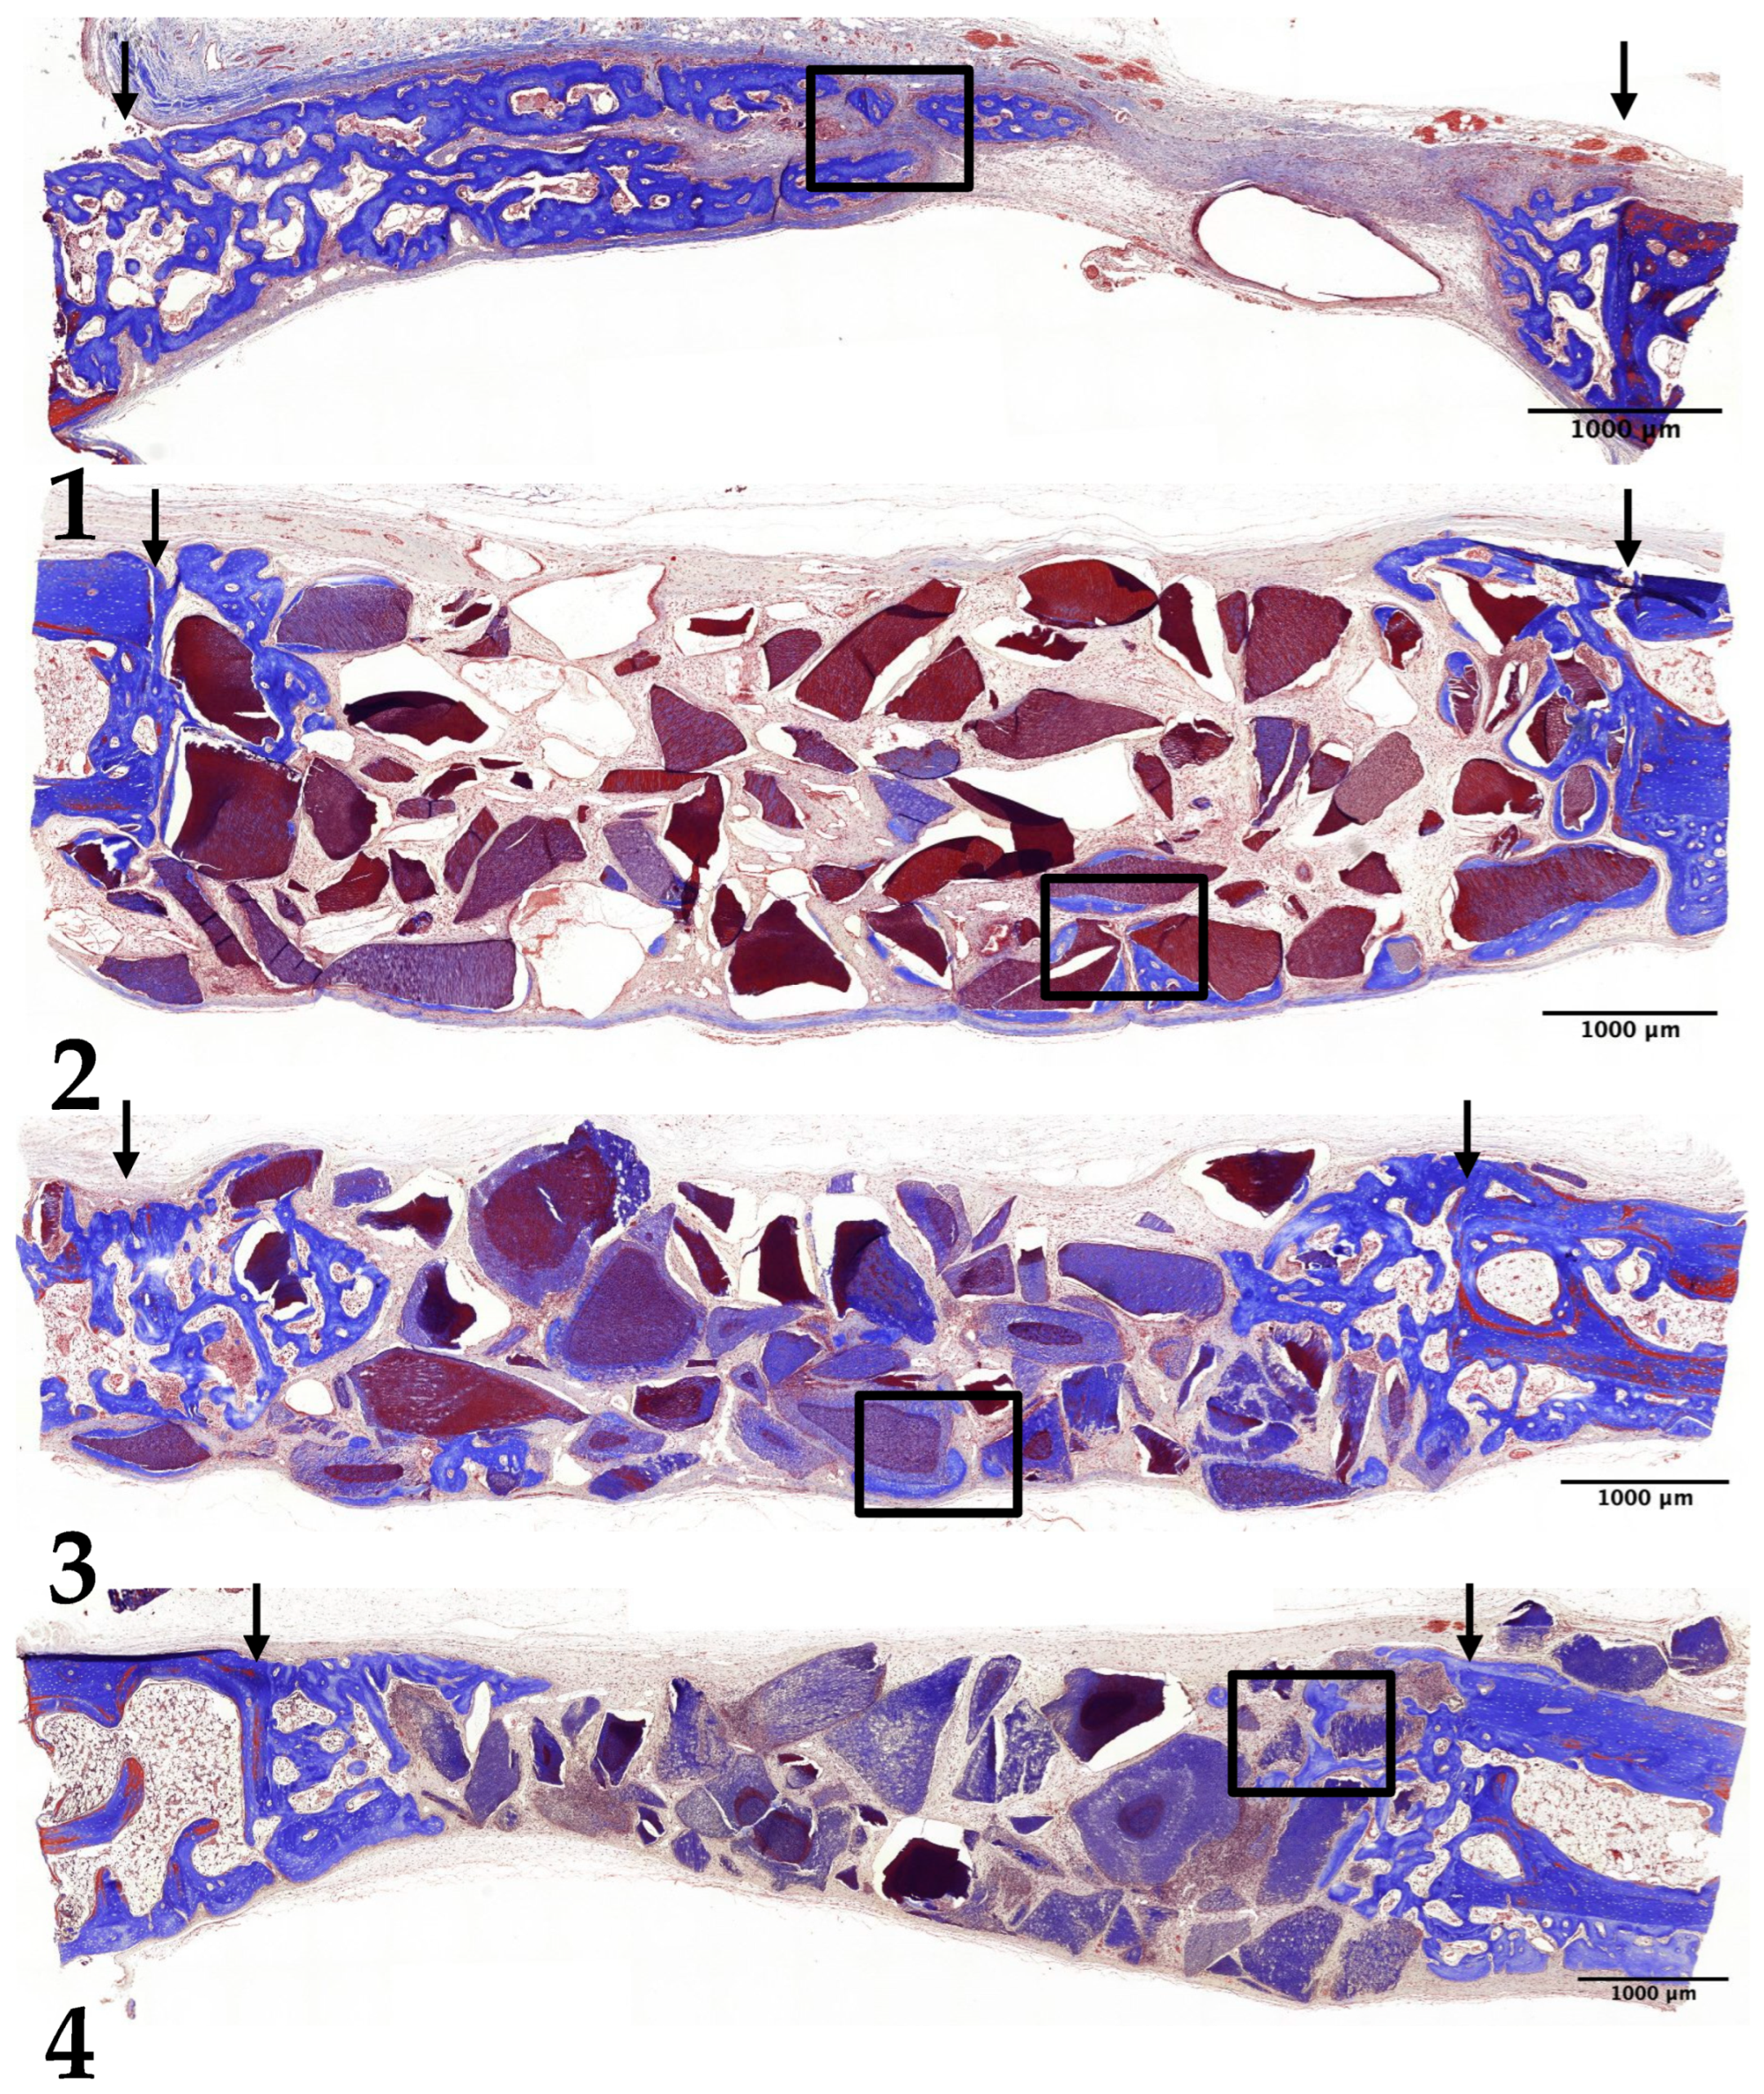

3.2. Two-Week Results

3.3. Four-Week Results

3.4. Eight-Week Results

3.5. Histomorphometric Analysis: New Bone Formation

3.6. Histomorphometric Analysis: Decrease in Remaining Graft Material Area

3.7. Histomorphometric Analysis: Quantifying Changes in Bone Marrow Area